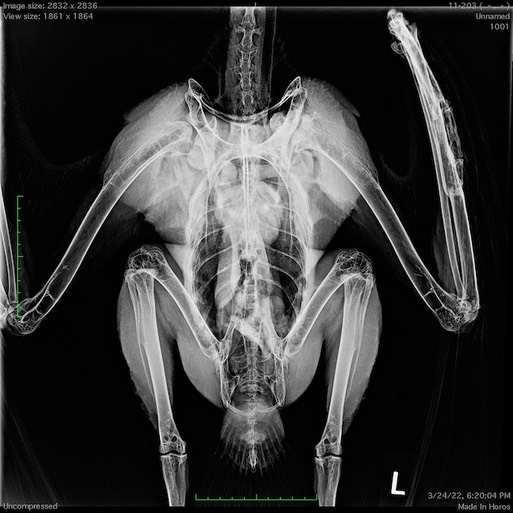

Before being moved into his new mew, we brought Patriot inside for a physical exam, blood work and radiographs. Eleven years ago he was badly injured when hit by a car. There is still evidence of his wing injury. In the radiograph below you can see the left shoulder muscles are smaller than the right shoulder muscles because he doesn’t use the left wing as much.

There is also still evidence of the healed ulna fracture.